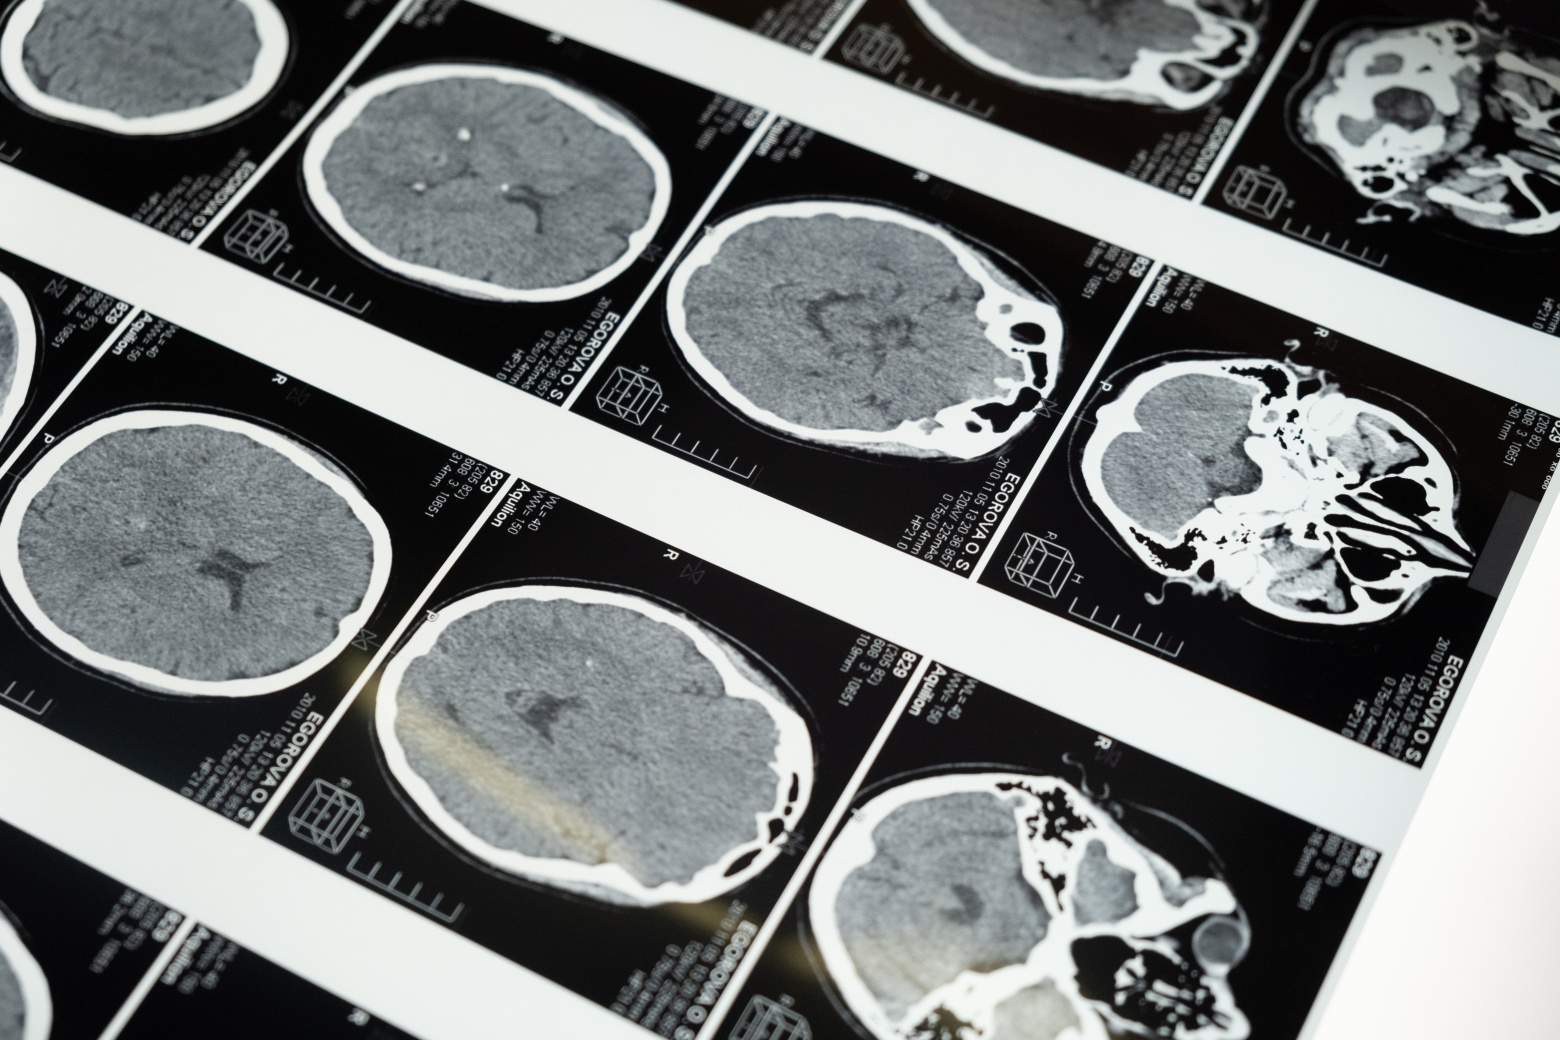

뇌경색은 제 때 대응하지 않으면 사망하거나 장기적으로 심각한 결과를 초래할 수 있는 응급 질환입니다. 초기에 증상을 신속하게 치료하지 않으면 심각한 합병증과 함께 장애로 이어질 뿐만 아니라 사망할 수도 있으므로 조기 치료 가장 중요합니다. 뇌경색의 전조증상과 초기증상과 치료방법 예방방법을 알아보겠습니다.

시간이 지남에 따라 증상이 호전될 것이라고 생각하고 넘어가지만 확인되지 않은 약물을 복용하거나 대충 대처하는 것은 위험합니다. 뇌경색 발병률은 계속해서 증가하고 있는데, 일단 발병하면 약 40~60%의 환자가 장기적인 후유증을 경험하게 되므로 예방이 중요합니다.

사람들은 일반적으로 뇌출혈에 비해 치료를 받을 수 있는 시간이 길다고 생각하지만 한 번 뇌혈관이 막히면 뇌세포가 죽기 시작하므로 3시간 이내에 혈전용해제를 맞거나 뇌세포 괴사를 예방하는 시술을 받는 것이 중요합니다.